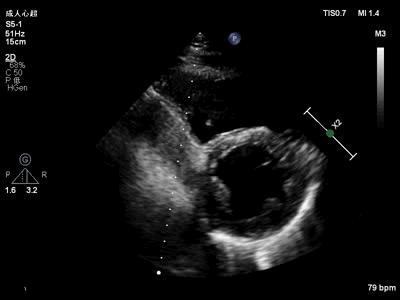

接诊医生对患者进行仔细的体格检查后发现心界向左扩大,建议行超声心动图检查(图2~图5)。首诊的超声医生发现该患者并非左心扩大,而是右心室增大,但不能用右心扩大的常见病因解释,且伴有心脏整体活动的异常(局部运动亢进),遂请超声心动图室杜鑫主任会诊。

图2. 胸骨旁左心室长轴切面显示右心室扩大,左心室后壁运动幅度显著增大,室间隔运动幅度减低